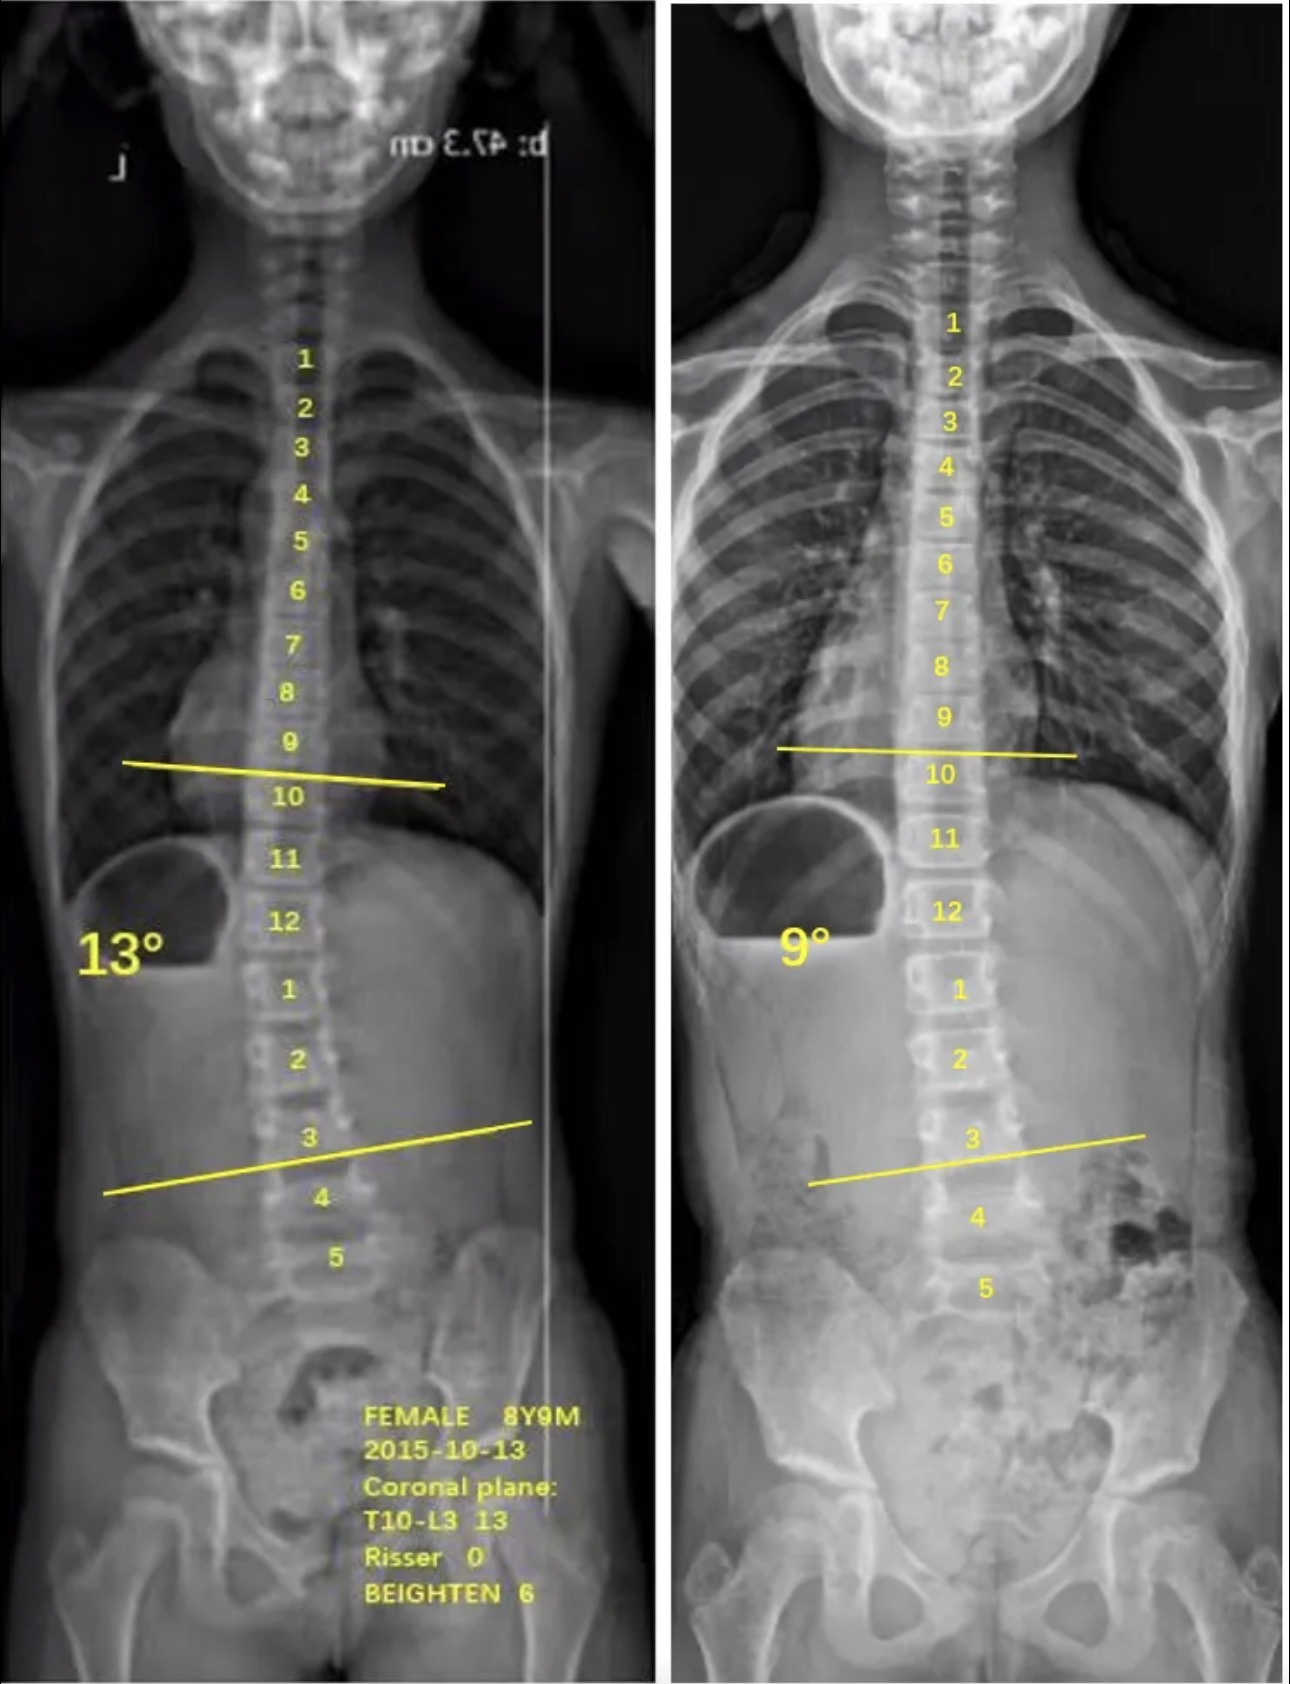

衷德脊柱,我们只关注侧弯保守治疗~

Zhongde Spine, bending no breaking ~